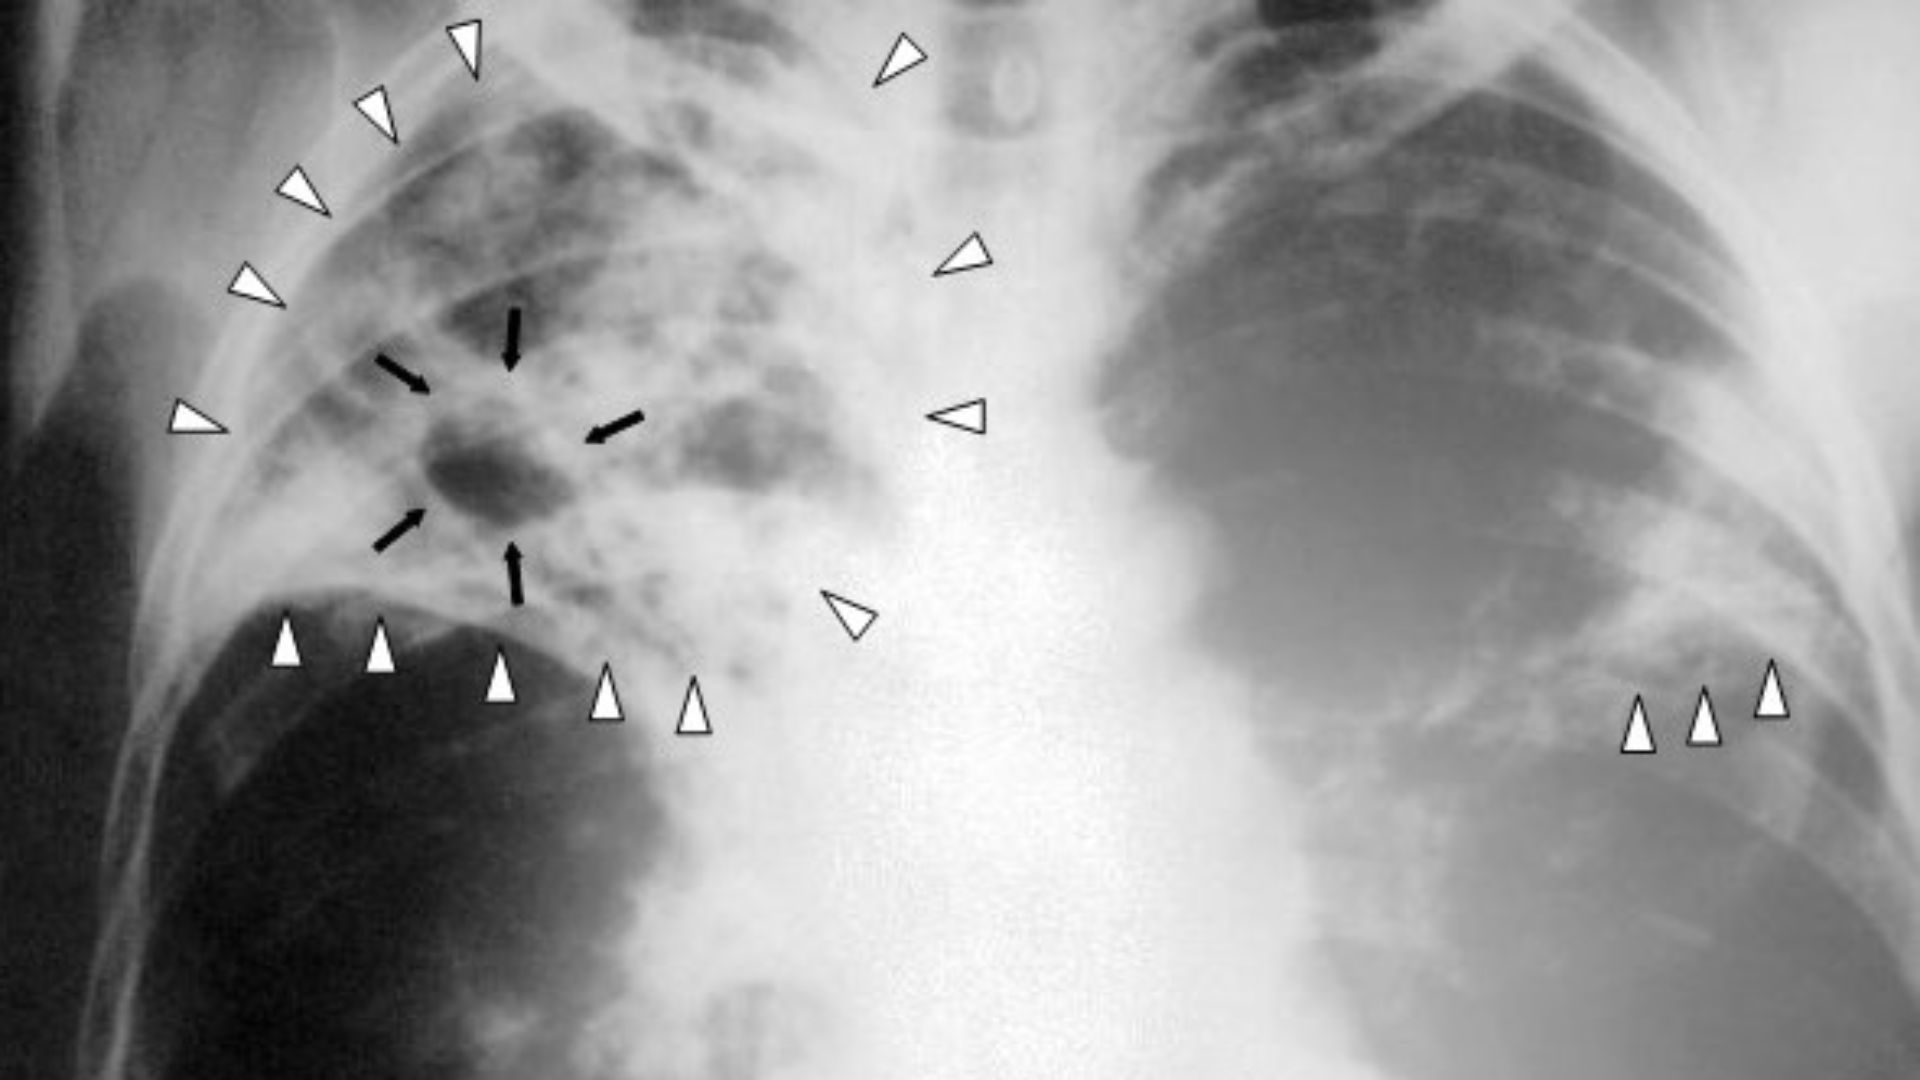

7. Multi-Drug Resistant Tuberculosis

While regular tuberculosis is curable, extensively drug-resistant TB strains require two years of multiple antibiotics with tough side effects, and success rates pale at around 50%. The bacteria develop resistance faster than new drugs appear.